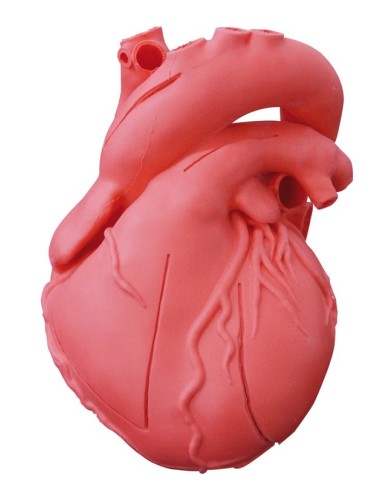

Modello di cuore di alta qualità scomponibile in 5 parti

Modello di cuore di alta qualità scomponibile in 5 parti

La parete anteriore del cuore è staccabile per poter vedere i ventricoli.

Modello anatomico di cuore, ingrandito 2 volte, su cavalletto

Realizzato in stampa 3D ad elevatissima risoluzione a colori.

Realizzato in stampa 3D ad elevatissima risoluzione a colori.